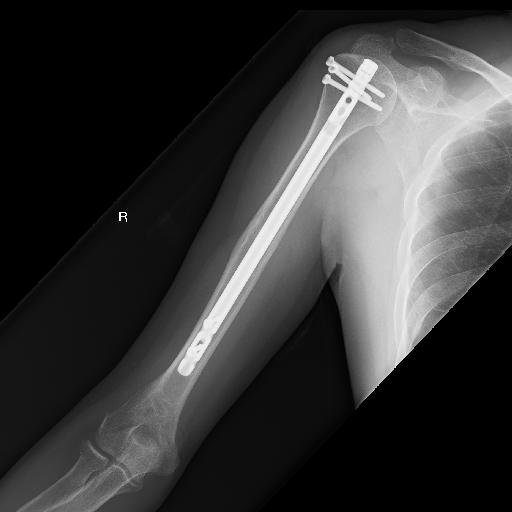

今年の初め頃、通勤途中に車に跳ねられまして、右上腕骨折の重傷を負ってしまいました。何とも痛々しいバキ折れ方をしております。ホントに痛かった(TT)

手術の結果、改造人間になってしまった私。

そして、8カ月以上の療養・リハビリの末、久々に投げ釣りに行ってきましたが、体力が衰えているのもありますが、後遺症が残って満足に投げ竿が振れません。